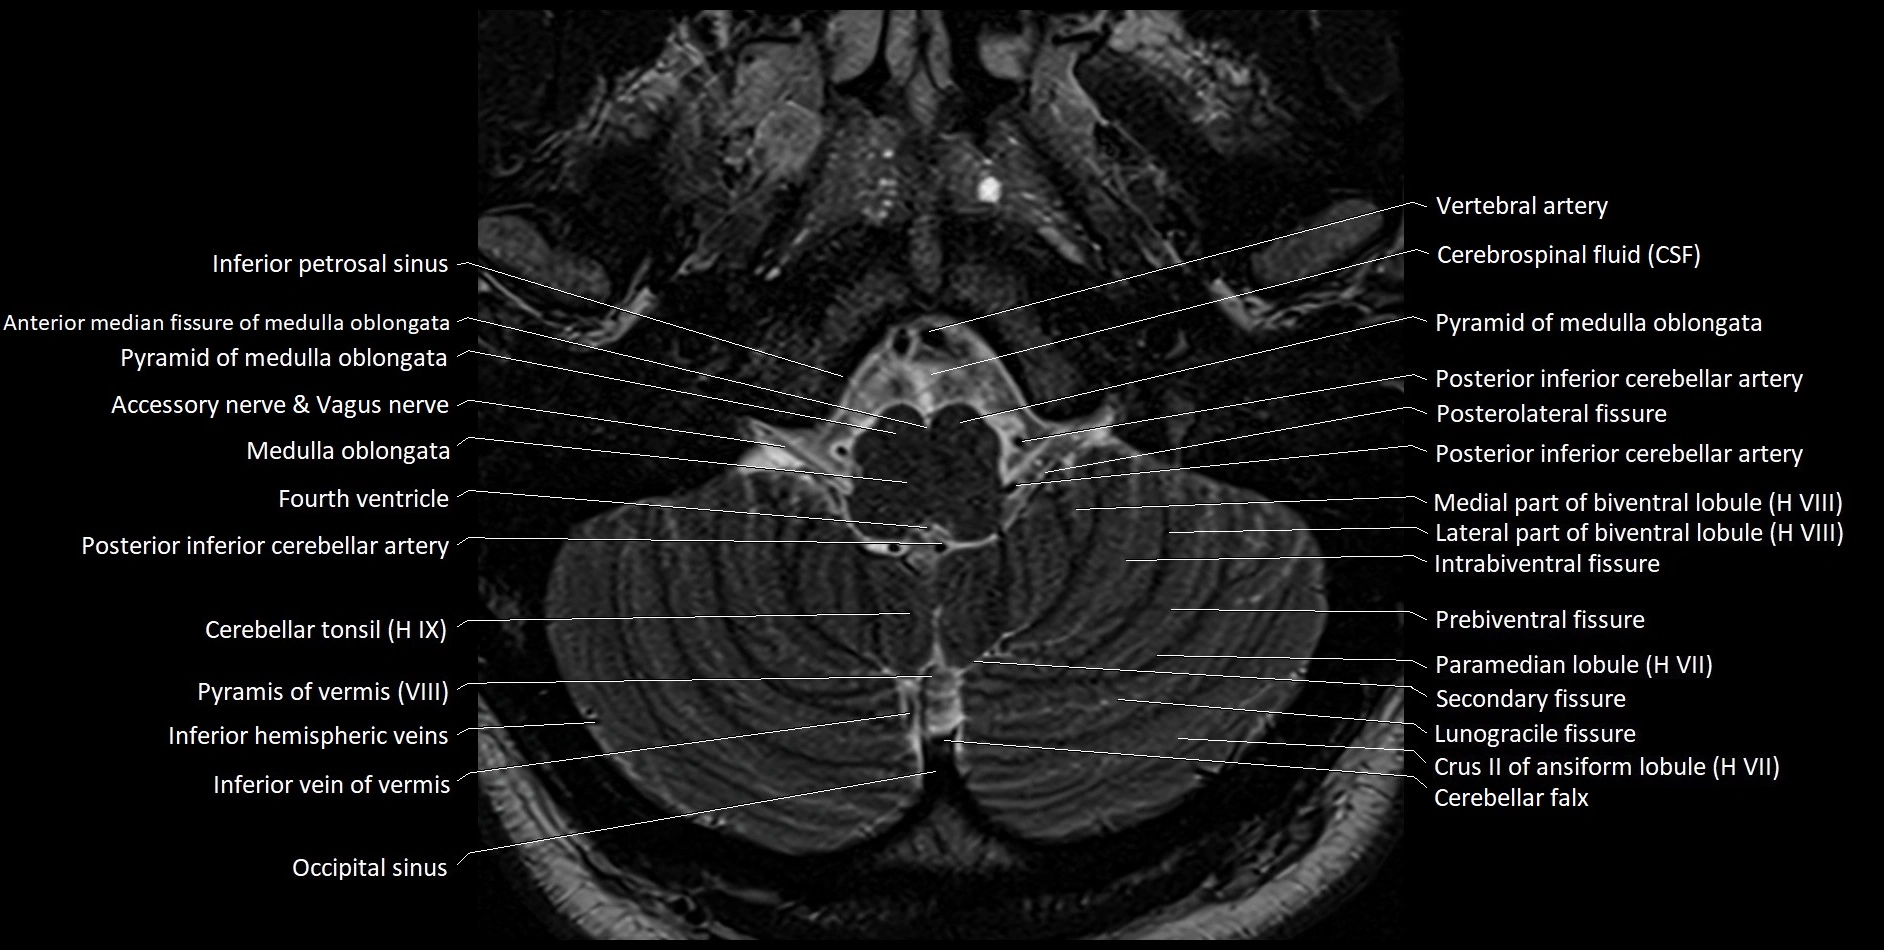

- Inferior petrosal sinus

- Pyramid of vermis (VIII)

- Pyramis of vermis

- Cerebellar tonsil (H IX)

- Tonsil of cerebellum

- Posterior inferior cerebellar artery

- Posterolateral fissure

- Intrabiventral Fissure of Biventral Lobule

- Lateral part of biventeral lobule

- Medial part of biventeral lobule

- Prebiventral fissure

- Paramedian lobule (HVII) of cerebellum

- Secondary fissure

- Lunogranicile fissure of cerebellum

- Crus II of ansiform lobule of cerebellum

- Cerebellar falx

- Inferior hemispheric veins of the cerebellum

- Inferior vein of vermis

- Occipital sinus